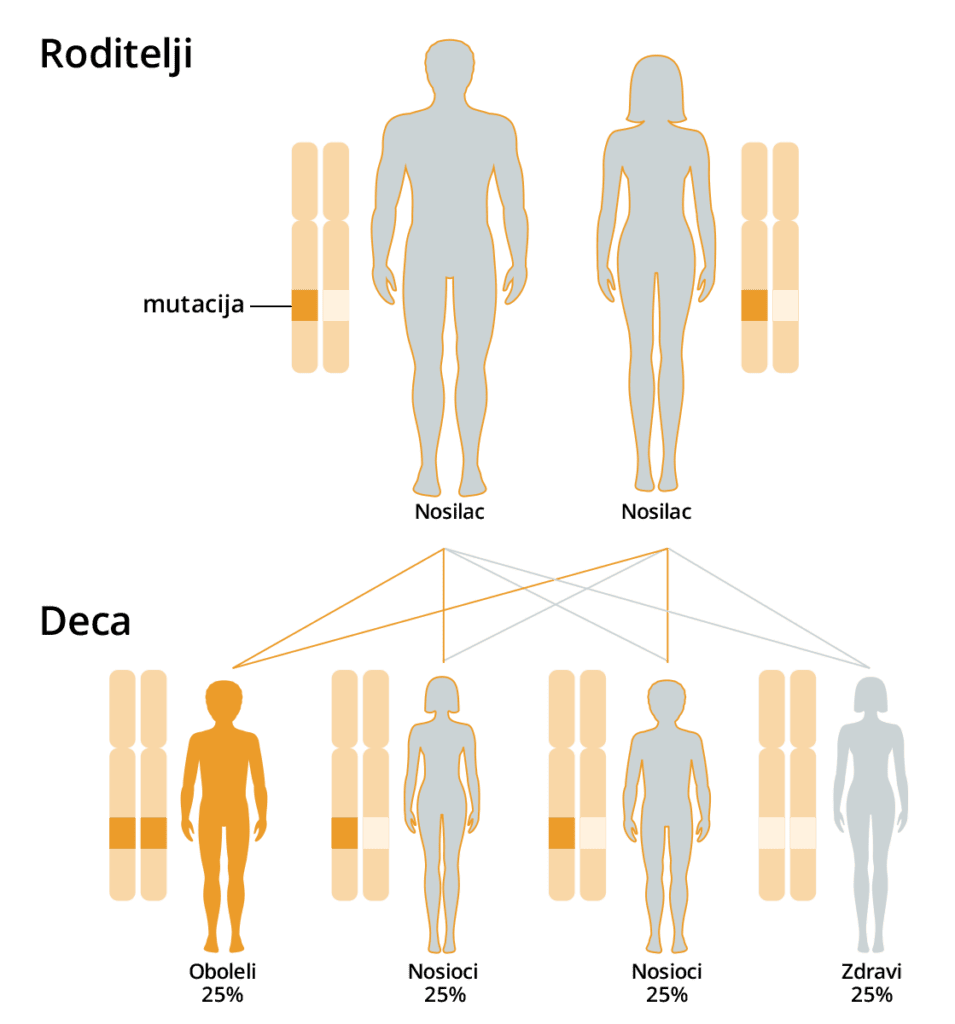

Testom se vrši skrining autozomno recesivnih, autozomno dominantnih i bolesti povezanih sa X hromozomom.

Većina dece sa naslednim oboljenjima se rađa zdrava, a prvi simptomi bolesti se javljaju tek nakon nekoliko nedelja ili meseci, dok su roditelji ugavnom potpuno zdravi i bez ikakvih tegoba.

Kod dominantnih bolesti RIZIK ZA DECU JE 50% ILI VEĆI I ZAVISI OD STATUSA RODITELJA.